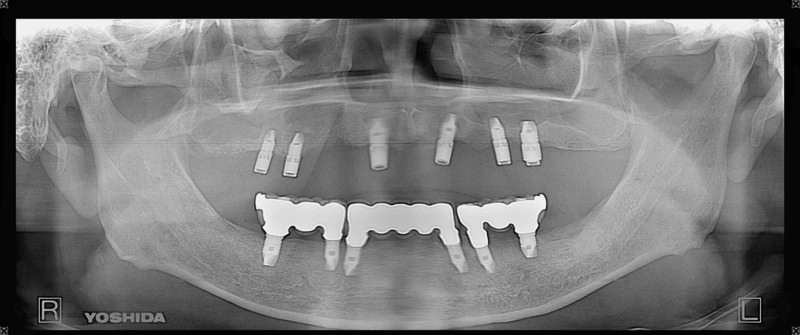

症例140代 男性 主訴 奥歯に歯を入れたい、しっかり噛みたい

治療前

治療後(5年経過)

※説明

主訴 奥歯がない為、食事が不自由である。入れ歯は煩わしいので、固定制のインプラントにして欲しいと訴え来院。口腔内全体で6本のインプラントを埋入。仮歯にて神経筋機構、顎関節のバランスを整え、リハビリを経て、約5ヶ月後にジルコニアを装着。

リスクとしては、外科的侵襲がある。デメリットは、保険外診療の為、経済的負担がある。

費用 316万(税込) (オペ・仮歯・最終補綴物まで含む)